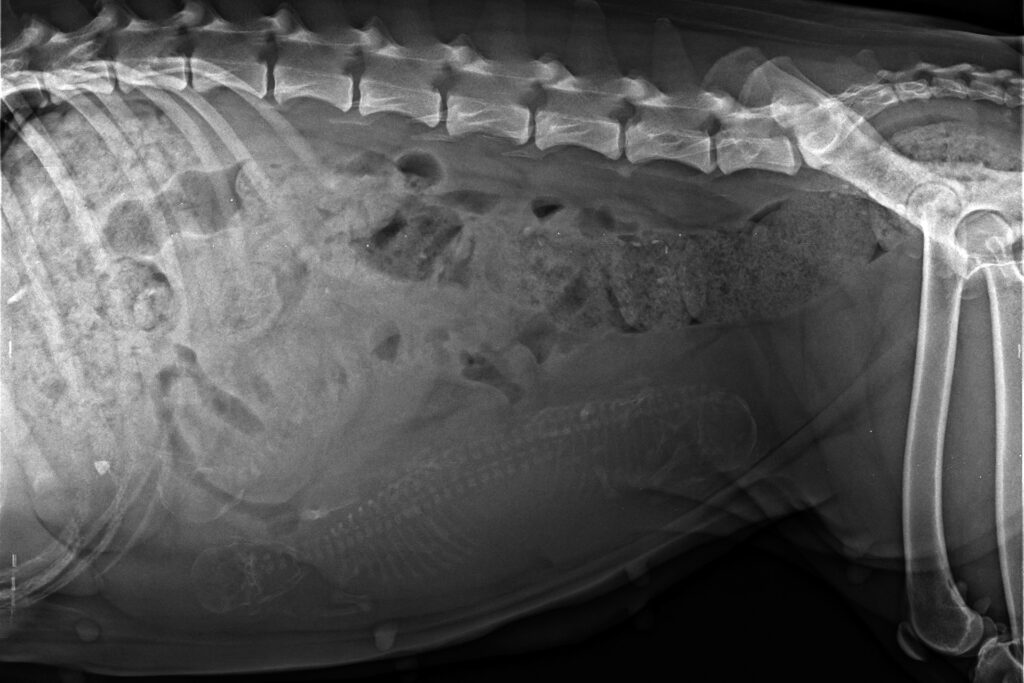

A few days before Christmas we did an x-ray to be sure about the number. This time, three puppies were clearly visible.

Opra was getting quite big, so we had been expecting more than three. She had no edema and apart from moving a bit clumsy, she was still quick on her feet.